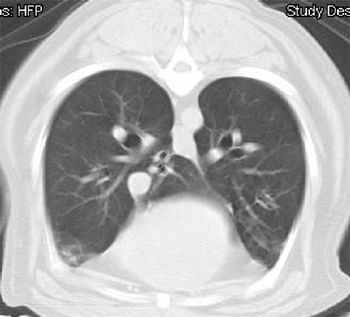

Pneumothorax is defined as free air in the pleural space. Normal intra-pleural pressure is about - 5 cmH20, which means that in order to equilibrate pressures, air from either the atmosphere, or the lung will equilibrate rapidly with the pleural space. Pneumothorax can be further characterized as traumatic, spontaneous and iatrogenic.

The pleural space is defined as the area between the lungs and the chest wall. Normally there is no soft tissue or free air present in this space. A very small amount of fluid (undetectable on radiographs or ultrasound) may be present within the thoracic cavity. Clinical signs of pleural space disease include tachypnea or difficulty breathing.

Pulmonary edema is defined as the accumulation of abnormal amount of extravascular lung water. Pulmonary edema may range from clinically insignificant to life-threatening. Pulmonary edema forms when there is an alternation in the balance of Starling forces (hydrostatic and colloid osmotic) between the interstitium and pulmonary capillary beds that favors increasing filtration to the interstitium. Increased capillary hydrostatic forces will result in a low protein edema fluid while lowered colloid osmotic forces will promote a high protein edema fluid.